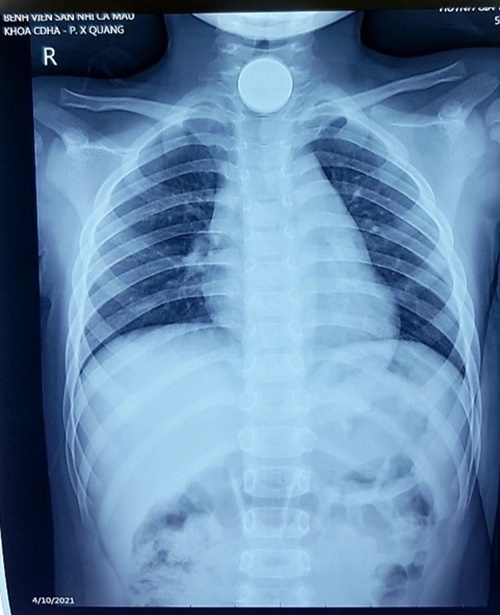

Hình ảnh chụp X-quang của bệnh nhi mắc đồng xu ở thực quản. (Ảnh: BV) |

Bé được đưa tới cấp cứu tại một phòng khám tư nhân trước khi chuyển tới bệnh viện Sản - Nhi Cà Mau. Hình chụp X-quang cho thấy đồng xu mắc kẹt ở thực quản đoạn cổ - ngực.